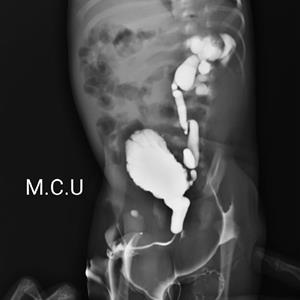

MCUG ::::; MICTURATING CYSTO URETHROGRAM

IT IS A SERIAL LIVE DYE STUDU OF URETHRA,URINARY BLADDER,URETERS UP TO KIDNEY

TO SEE VESICO-URETRIC REFLUX.